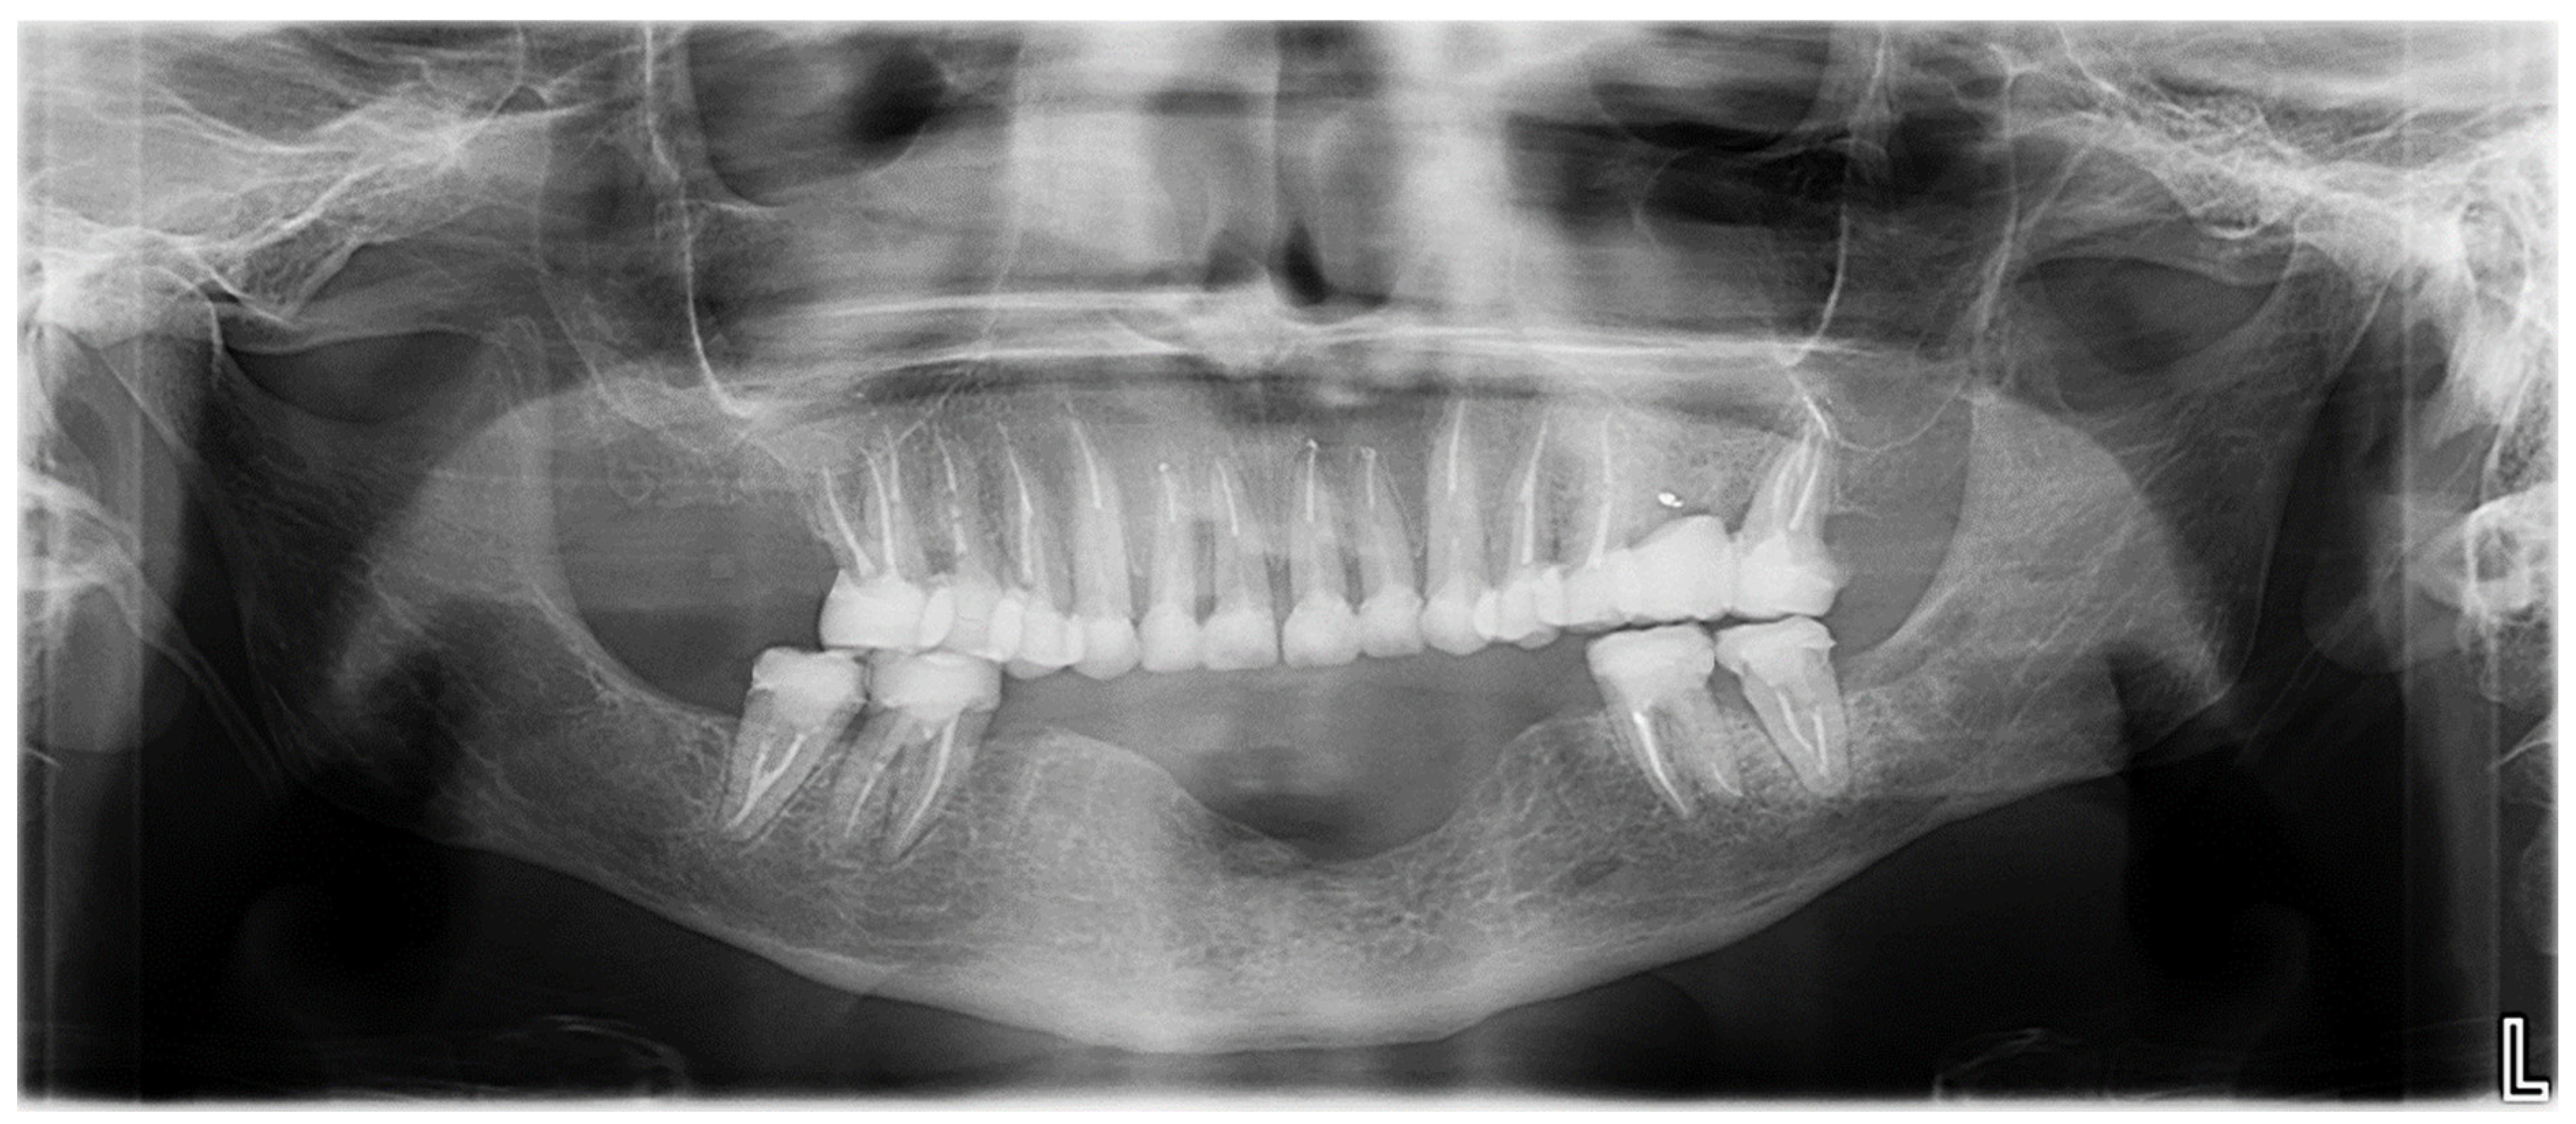

2.4.3. Step 3: Definitive Prosthetic Rehabilitation

2.5. Outcomes and Follow-Up